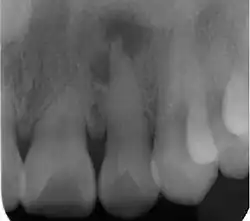

| Radiograph (X-ray) showing microdontia. Note also periapical lesion on the maxillary left lateral incisor. | |

Microdontia is a condition in which one or more teeth appear smaller than normal. In the generalized form, all teeth are involved. In the localized form, only a few teeth are involved. The most common teeth affected are the upper lateral incisors and third molars.

Localized microdontia is also termed focal, or pseudo-microdontia. A single tooth is smaller than normal.[3] Localized microdontia is far more common than generalized microdontia,[2] and is often associated with hypodontia (reduced number of teeth).[1] The most commonly involved tooth in localized microdontia is the maxillary lateral incisor, which may also be shaped like an inverted cone (a "peg lateral").[3] Peg laterals typically occur on both sides,[2] and have short roots.[2] Inheritance may be involved,[2] and the frequency of microdontia in the upper laterals is just under 1%.[1] The second most commonly involved tooth is the maxillary third molars,[3] and after this supernumerary teeth.[3]